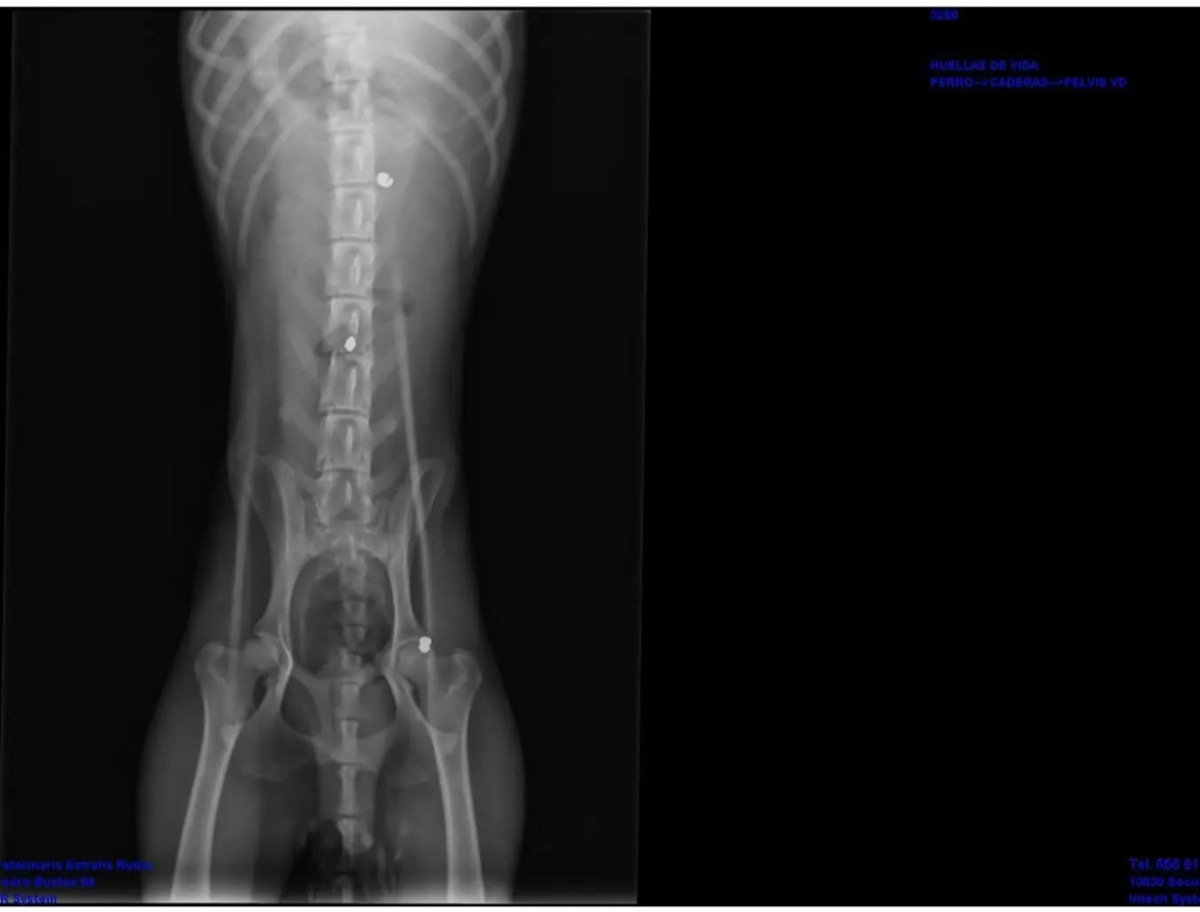

Regaliz – eine Kämpferin mit großem Herzen - Regaliz ist eine etwa 5–6 Jahre alte Mischlingshündin mit mittellangem, schwarzem Fell und einer Schulterhöhe von ca. 48 cm. Trotz ihres schweren Schicksals hat sie sich ihre Lebensfreude und ihre Liebe zu Menschen bewahrt. Ihre Geschichte - Im April 2023 erhielten wir einen Hinweis auf Regaliz: Tagelang hatte sie sich in einer nahegelegenen Stadt durch die Straßen geschleppt, ohne ihre Hinterbeine bewegen zu können. Beim Tierarzt brachte ein CT-Scan die grausame Wahrheit ans Licht – Regaliz war angeschossen worden. Drei Kugeln steckten in ihrem Körper, eine davon im Rückenmark. Man hatte sie schwer verletzt zurückgelassen, offenbar in der Annahme, sie würde sterben. Noch im Jahr 2023 wurde sie in einer sechsstündigen Operation operiert. Zwei Kugeln konnten entfernt werden, die Dritte im Rückenmark jedoch nicht. Regaliz überlebte und wurde von einem Pärchen adoptiert. Wie hatten wir und die Freiwilligen der Perrera sich gefreut, dass die süße Maus ein liebevolles Zuhause fand!! Leider ist die Beziehung zerbrochen, und keiner von beiden kann sich weiterhin um sie kümmern und so braucht Regaliz, die in ihrem Zuhause Pepa genannt wurde, ein neues Zuhause. Sie ist eine absolut menschenfreundliche Hündin. Regaliz ist sozial, offen und genießt Nähe und Aufmerksamkeit - sie liebt es Zeit mit ihrem Menschen zu verbringen! Mit anderen Hunden – egal ob Rüde oder Hündin – kommt sie gut zurecht, ebenso mit Katzen. Sie ist super-verträglich, super-angenehm und einfach super-besonders🥰. Insbesondere ihre Lebensfreude ist bemerkenswert: Die hübsche Hündin mit dem schwarzen Fell hat gelernt, sich mit einem Rollstuhl fortzubewegen, liebt es zu rennen und ist begeistert, wenn sie mit einem Ball spielen darf. Ihre gute Laune ist ansteckend und sie ist eine Hündin, bei der stetig die Sonne im Herzen scheint. Durch die im Rückenmark verbliebene Kugel leidet Regaliz an einer Bleivergiftung und ist dauerhaft gelähmt. Sie hat weder Bewegungsfähigkeit noch Gefühl in den Hinterbeinen. Zudem ist sie inkontinent und braucht Unterstützung beim Urinieren und Koten. Mit der richtigen Pflege und Routine kommt sie damit jedoch gut zurecht. Regaliz sucht ein Zuhause bei Menschen mit Herz, Geduld und Verantwortungsbewusstsein – Menschen, die bereit sind, sich auf die besonderen Bedürfnisse einer gehandicapten Hündin einzulassen und ihr die Liebe und Sicherheit zu geben, die sie so sehr verdient. Sie gibt diese Liebe tausendfach zurück. Regaliz ist der Beweis dafür, dass Lebensfreude und Vertrauen selbst nach schlimmsten Erfahrungen weiterleben können. 💛